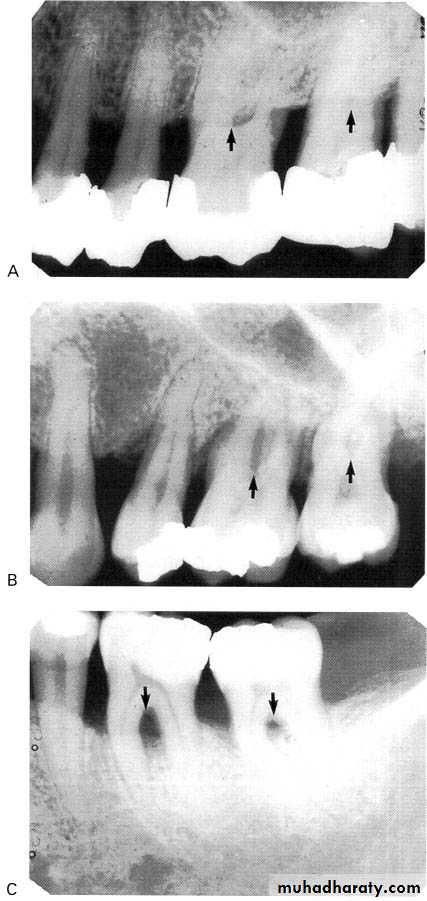

3.Furcation involvements:

Bone loss in the furcation area of the roots which is evidence of advanced disease in multirooted

teeth.

Initially seen as widening of the PL space at the crest of

the furcation . As lesion progresses, the bone

loss progresses apically.

Mild/moderate/sever.